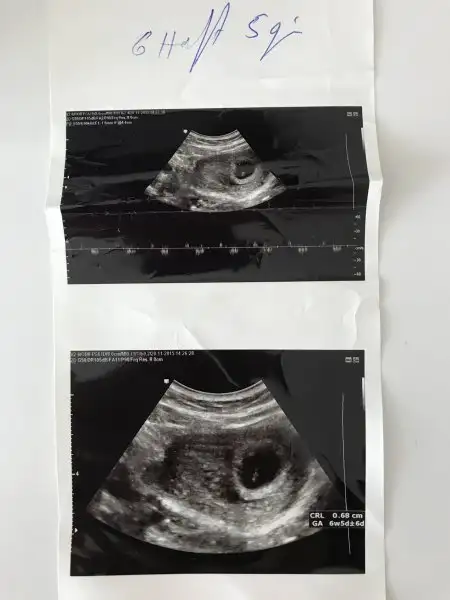

Bu da bir örnektir oğlumun ultrasonu

• A3D7F61F-1294-4664-A971-15D30CC26C58.webp

13,2 KB · Görüntüleme: 356